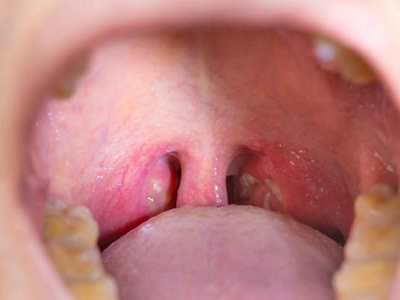

扁桃体结石多呈灰白色,表面粗糙,质地坚硬。部分患者可自觉咽部有异物,结石较大者,进食可出现阻挡感。并发扁桃体炎症时,可出现患侧扁桃体肿大、咽痒、刺激性咳嗽等症状,甚则可出现咽喉肿痛、吞咽困难、发热等全身症状。

扁桃体内可发现灰白色、质地较硬的细小沙石,或可在肿大的扁桃体内触及较硬的肿块,触时有微痛感。